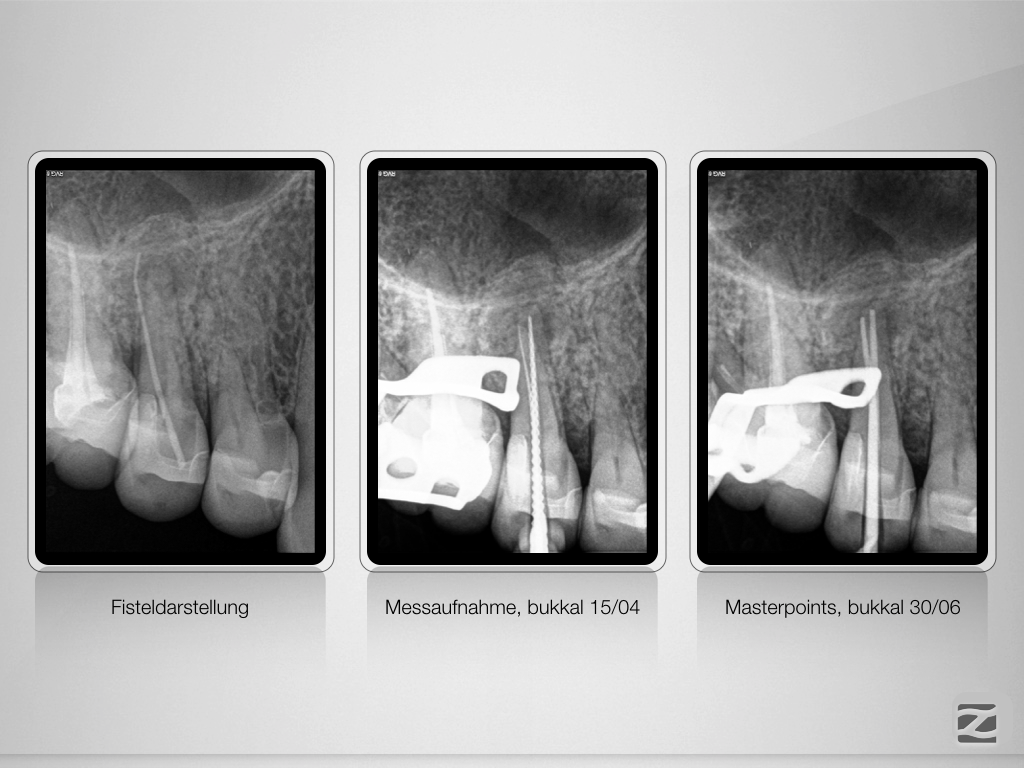

Wie weit ist weit genug?